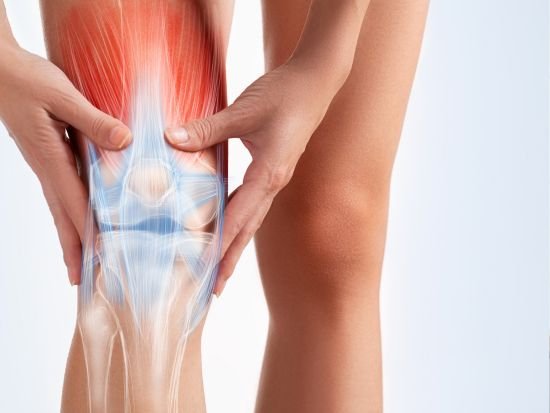

Sports Injury Rehab

खेल चोट पुनर्वास

Pain Management

दर्द प्रबंधन

Arthritis Care

गठिया का उपचार